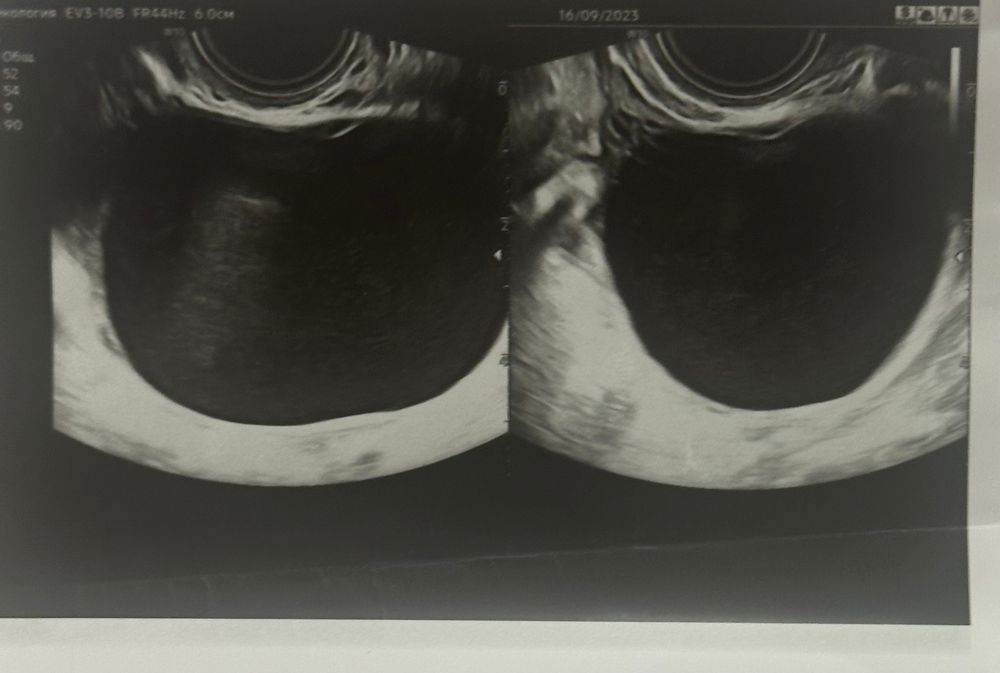

Всем привет. 4 месяца назад на узи обнаружили кисту размерами 6*5 см. Сказали что фолликулярная, назначили лечение. На следующий цикл киста совсем не изменилась, и по сей день она не уменьшилась ни на миллиметр. Что это может быть за киста? У кого было что-то подобное?

Если образование в яичнике не уходит в течение 3х циклов , то делаем мрт. Дифференциальная диагностика с серозной цистаденомой.

Разница на узи в толщине стенки. На обычном аппарате не углядеть. Можно экспертное узи сделать. Но золотой стандарт -мрт. Плюс, сдать на онкомаркеры (са125, he4)